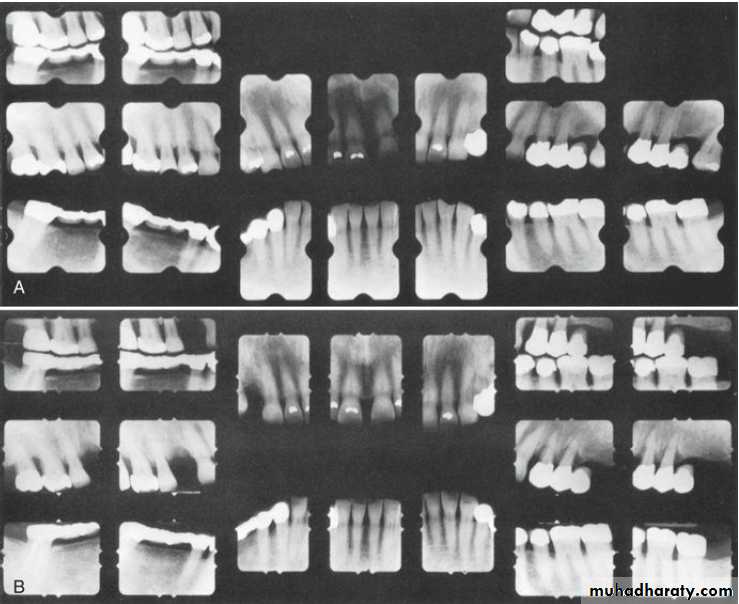

Radiographic examination must be individualized, depending on the initial severity of the case and the findings during the recall visit. These are compared with findings on previous radiographs to check the bone height and look for repair of osseous defects, signs of trauma from occlusion, periapical pathologic changes, and caries.